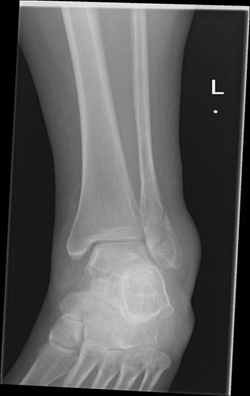

A 43-year-old female marathon runner presented with a stress fracture in the distal region of the fibula. She had been experiencing pain in her ankle for several weeks, and the pain had worsened recently. She was unable to run or walk without pain. The patient did not have any underlying osteometabolic pathologies and used an intrauterine device for contraception. She also underwent regular nutritional monitoring and maintained an adequate sleep schedule, which is crucial for bone health and overall recovery. X-rays and MRI confirmed the presence of a stress fracture.

The MRI showed significant edema and a clear fracture line in the distal fibula. Initially, she was placed in a walking boot and instructed to rest her leg, reducing weight-bearing activities to allow the bone to heal. After four weeks of rest, her pain had improved, but the fracture was not yet fully healed, as indicated by follow-up imaging. Given her active lifestyle and the need for a quicker recovery, the patient was started on teriparatide 20 mcg daily.

Her recovery was marked by a steady improvement in pain levels and functional outcomes, allowing her to resume her athletic activities with confidence. (Figure 1,2)